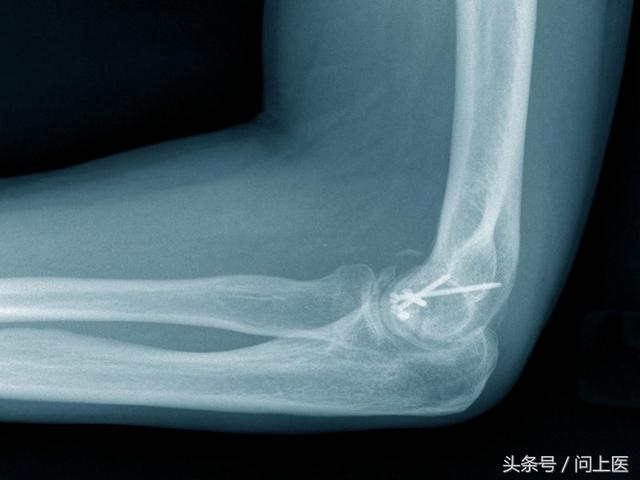

骨折病人护理措施及注意事项(骨折患者的日常护理)

导语:骨折就是指骨头或骨头的结构完全或部分断裂。多见于儿童及老年人,中青年也时有发生。“问上医”用美国家庭医生的智库告诉您骨折的预防及护理指南。